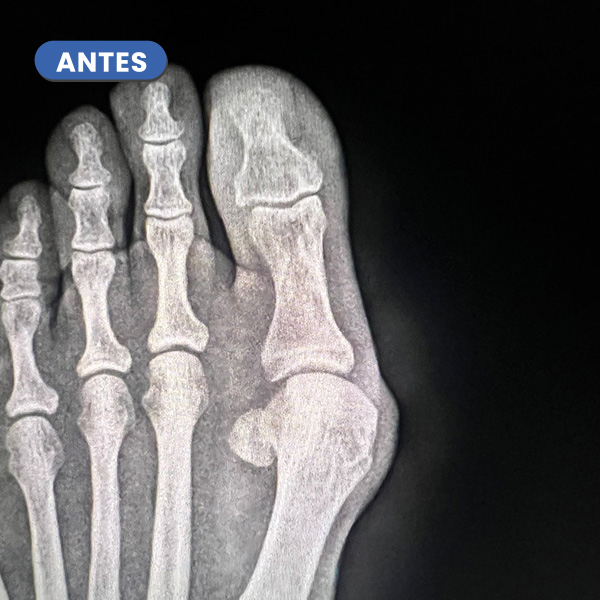

Casos reales resueltos con Cirugía de Mínima Incisión (CMI)

Te mostramos casos reales resueltos mediante cirugía de mínima incisión por el Dr. Rubén Lorca y su equipo.

Mueve las flechas para visualizar el antes y después.